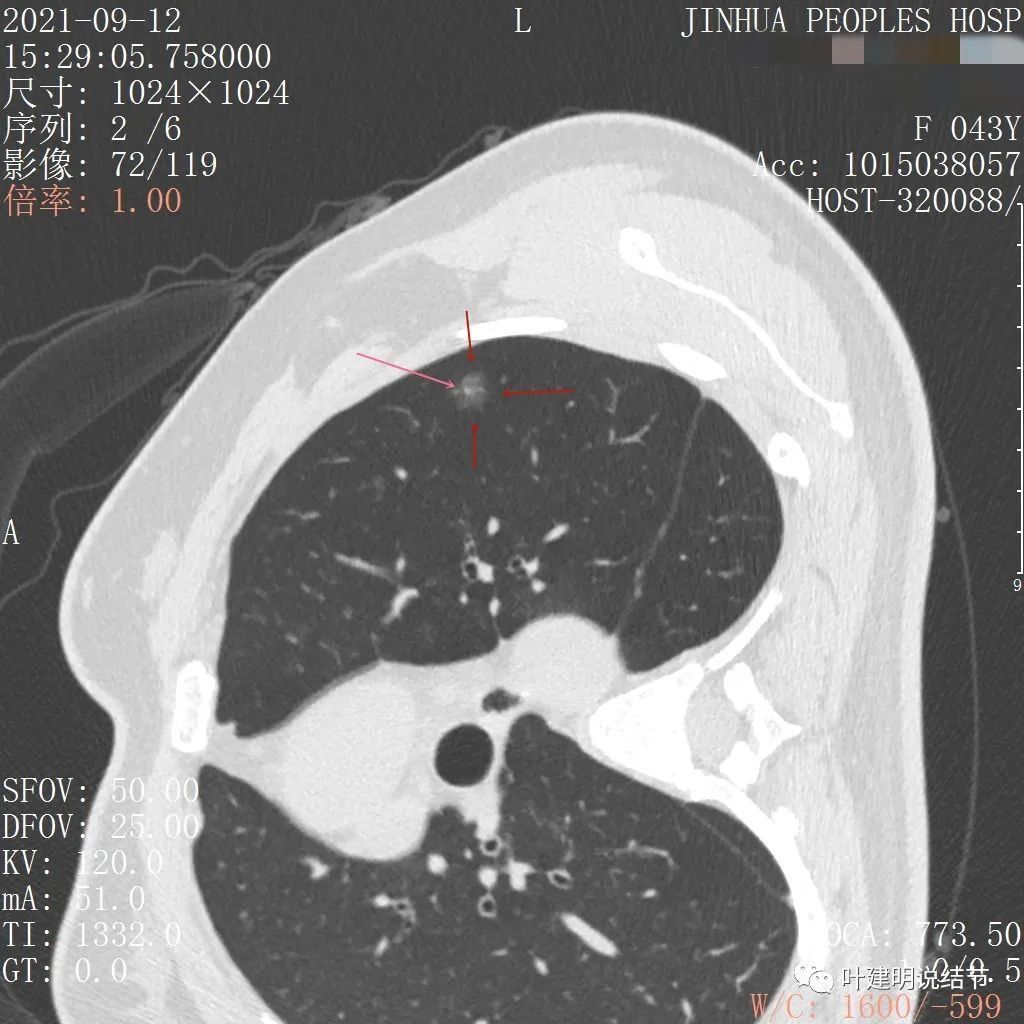

上图示病灶边缘磨玻璃成分有的区域密度过低(绿色箭头),事后回头来看,磨玻璃部分的密度过低,不容易是浸润性腺癌,而更符合原位腺癌

上图示瘤肺边界处显模糊(砖色箭头),病灶内部仍是有偏高密度的点状成分

上图层面也显示病灶边缘欠清,有些模糊,虽总体轮廓还是比较清晰

从以上靶扫描图像上看,给人的印象是肿瘤范畴的结节,是混合磨玻璃结节,但磨玻璃部分的密度偏低,有的边缘显模糊,中间有点状高密度,也有微小血管进入,应该至少微浸润性腺癌可能性大。持续存在已经2月余,位置又还靠边上的,可考虑手术切除。下面再来瞧瞧后处理重建的图像: